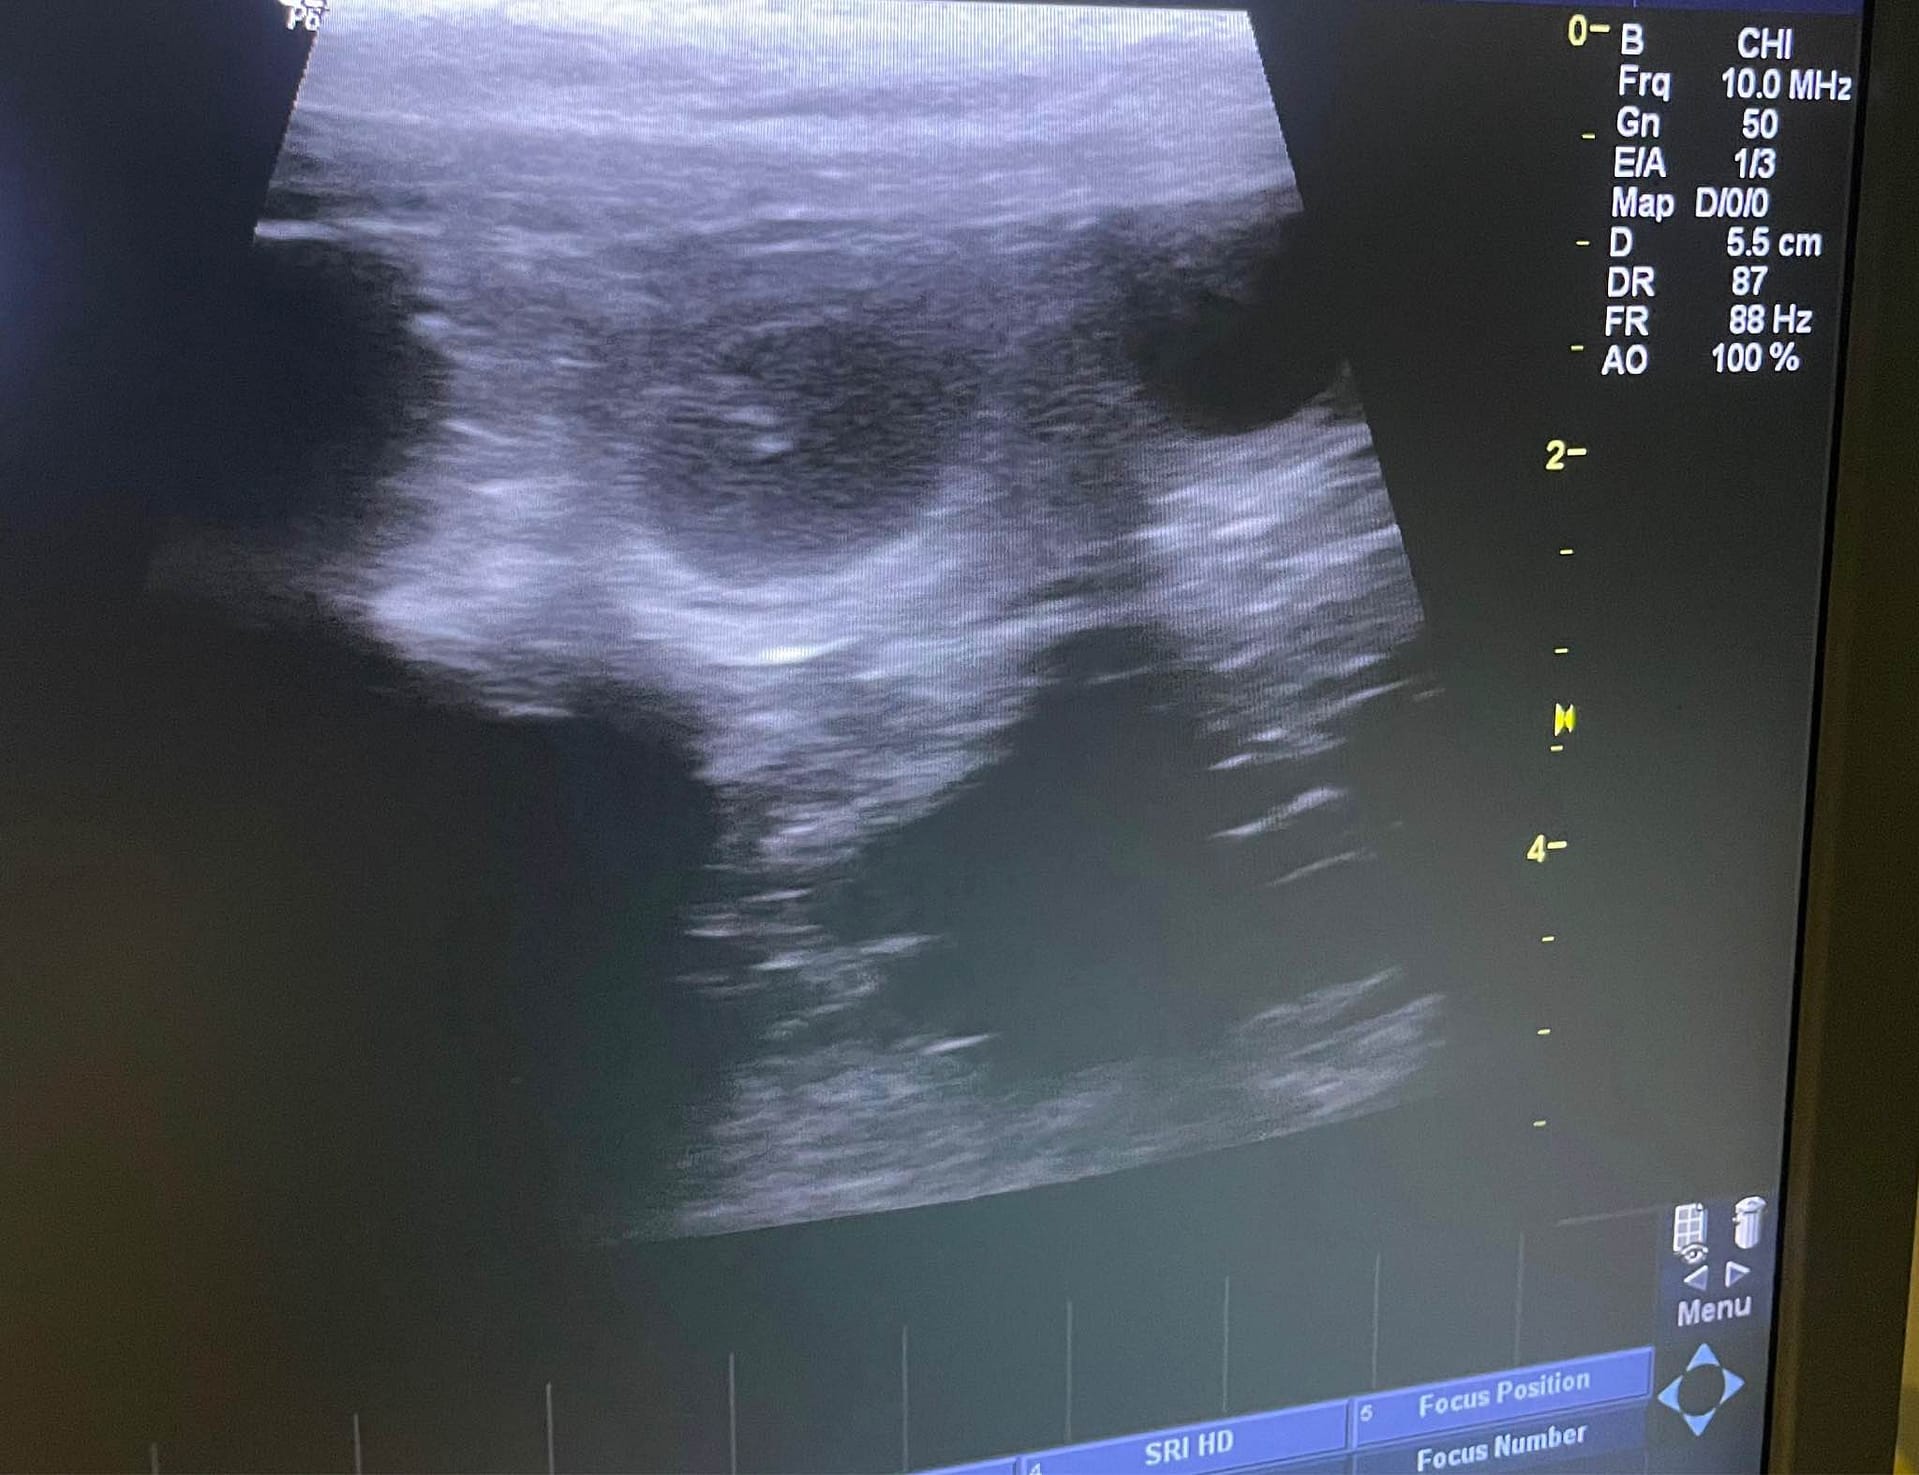

Irma on tiine! Tänään on 23 päivää ovulaatiosta, ja alkiot selvästi nähtävillä. Katsotaan lukumäärää vielä myöhemmin.

Tänään käytiin Irman kanssa Reprovetissä laskemassa pentusia. Irma oli kiltti tyttö ja Laura Linntamm löysi monta pientä pennunalkua. Irman tiineys on nyt toisella kolmanneksella ja absorptio on edelleen mahdollista. On aina yhtä jännää odottaa lopullista määrää <3